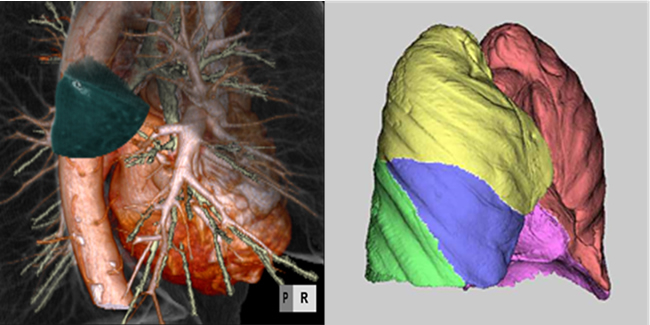

Diagnosis of chest CT has been assessed visually and qualitatively by radiologists, though multi-detector row CT (MDCT) and area-detector CT (ADCT) make them difficult to process only by manpower. In our group, a lot of CAD to quantify chest CT images has been developed by collaboration with respiratory medicine, thoracic surgery, image engineering, and enterprise. Main CAD system we have developed are as follows: 1) Shape classification, quantifying ground-glass opacity and 3D volumetry of lung cancer 2) Virtual bronchoscopy to guide bronchoscope 3) Virtual segmentectomy using 3D-CT angiography 4) Automated pulmonary lobar volumetry. Recently, we are approaching to CT diagnosis based on artificial intelligence.